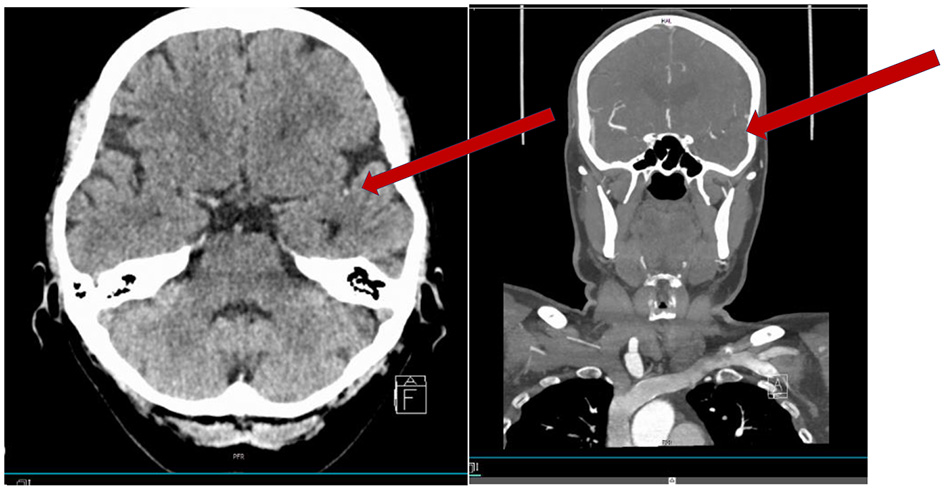

Figure 1. Fifty-nine-year-old woman with an acute onset of aphasia (NIHSS 1 disabling). CT scan showing a hyperdense vessel sign in M2 (arrow). CTA showing the occlusion in M2 (short in length).